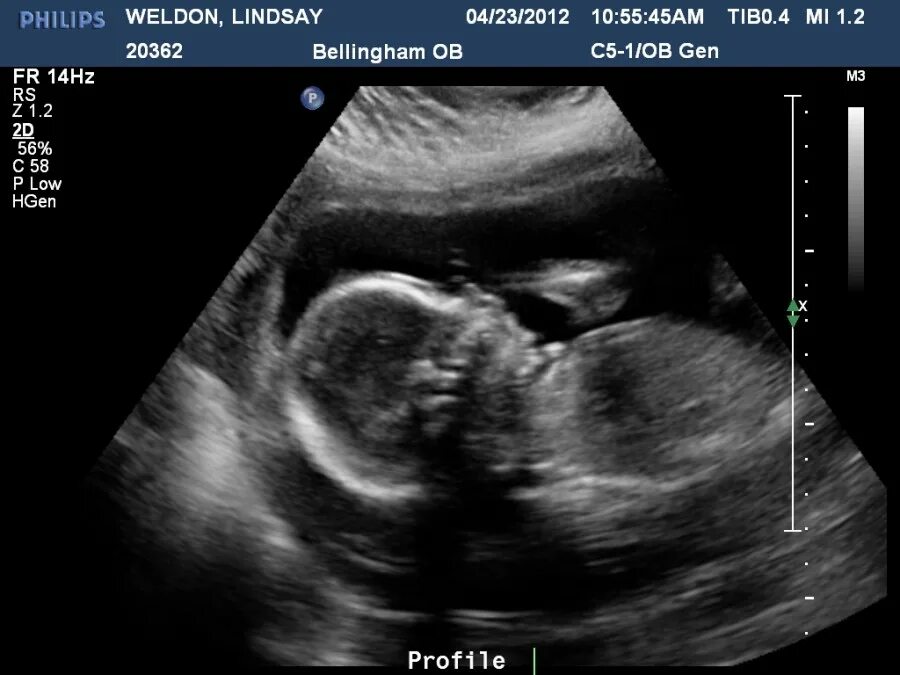

21 неделя беременности ощущения